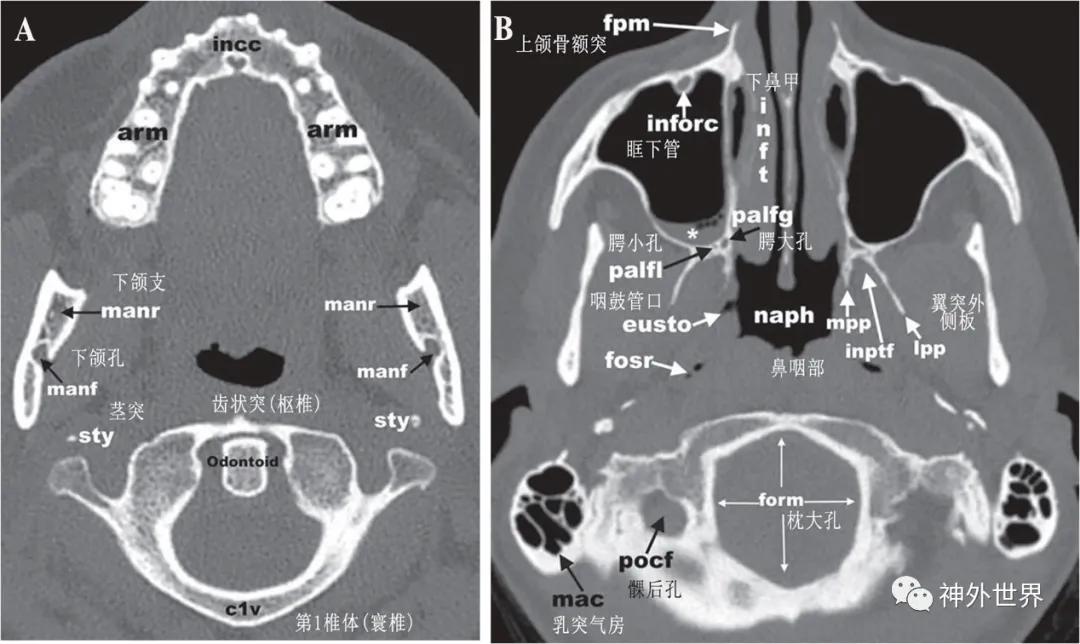

图3:颅底CT骨性横断面影像解剖